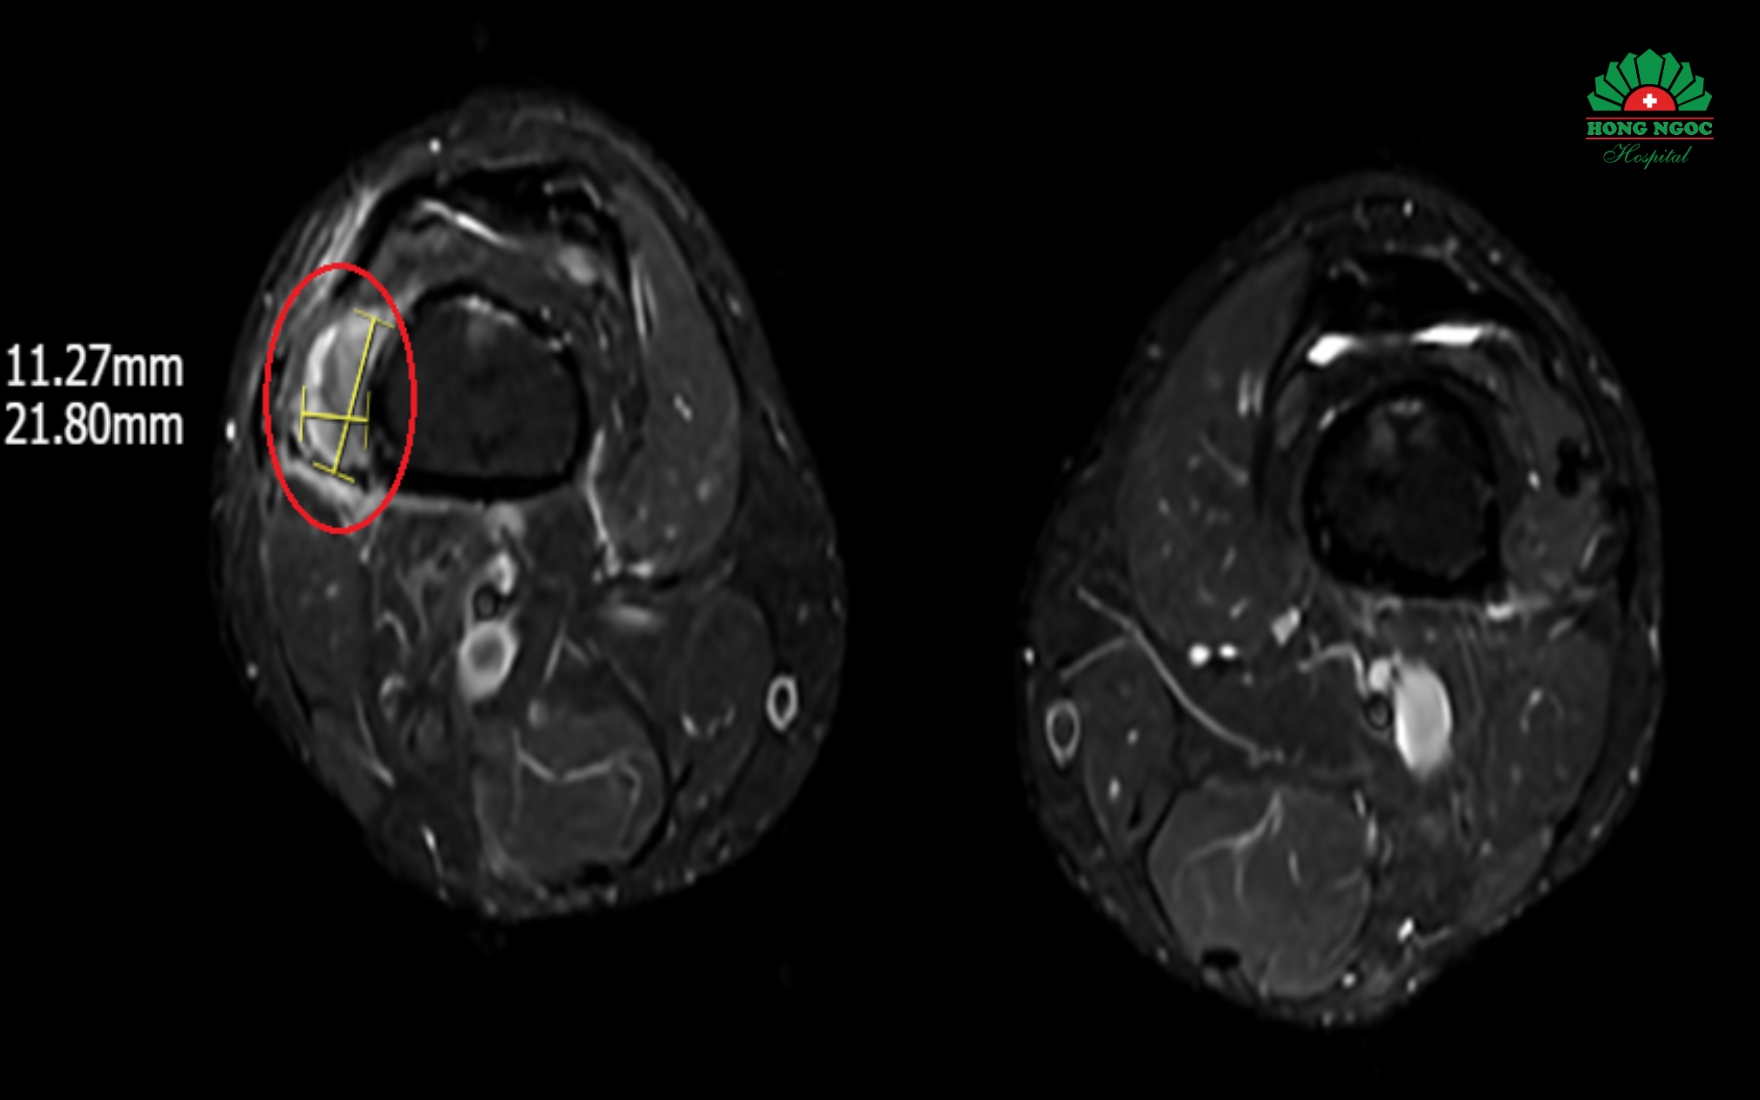

Hình ảnh khối u vùng vị trí phần mềm dưới đùi phải trên phim MRI

“Việc cần làm là phải xác định được vị trí của khối u để loại bỏ triệt để căn nguyên gây thiếu hụt phốt pho khiến xương giòn yếu. Tuy nhiên, thách thức của quá trình chẩn đoán là u tăng tiết FGF23 thường là u lành tính, nhỏ, không sưng đau và có thể ở xuất hiện ở bất kỳ vị trí nào trên cơ thể. Để củng cố chẩn đoán bệnh cần phải định lượng chỉ số FGF23 trong máu, tuy nhiên, ở Việt Nam hiện chưa có xét nghiệm này. Do đó, chúng tôi chỉ định bệnh nhân chụp PET/CT toàn thân với chất phóng xạ kết hợp chụp MRI, siêu âm, cuối cùng tìm thấy 1 khối u kích thước 1-2 cm vị trí phần mềm dưới đùi phải.” - ThS.BSNT Vân chia sẻ.